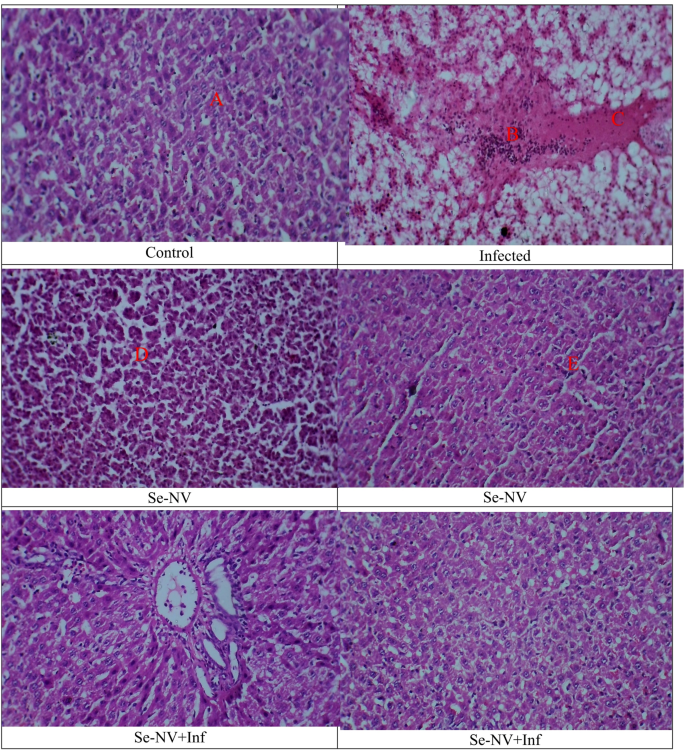

Figure 5 shows the different changes in the Tilapia liver. The control group showed hepatocytes in a uniform cord that extends from the central vein. The hepatocytes have a polygonal appearance as they have uniform cytoplasm and numerous nuclei. There are no symptoms of vacuolization, cellular degeneration, necrosis, or inflammatory infiltration demonstrated. Overall, the liver section showed healthy liver morphology. Furthermore, the Se-NV group has the same results, which showed liver in normal morphology without any notable necrosis, inflammation, steatosis, or fibrosis. In contrast, the infected group showed a change in liver morphology, including hepatocellular degeneration and vacuolization in the hepatic tissue (Fig. 5A). Furthermore, there was a breakdown in cytoplasm and lipid accumulation, which is considered a sign of fatty degeneration. Also, an inflammatory response was demonstrated by the presence of inflammatory cells within the hepatic cells surrounding the central vein (Fig. 5B). Overall, these findings indicate hepatic stress and decreased metabolic function, which may be caused by oxidative stress due to bacterial infection. Finally, in Se-NV + Inf, an improvement is shown in the arrangement of hepatocytes (Fig. 5C). in the liver, with little vacuolation and necrosis (Fig. 5D).

Liver histological changes in different groups. Treatments: control (injection with saline), infected (injection with bacteria), Se-NV (vaccine injection), and Se-NV + Inf (challenge with bacteria after vaccine injection).

The S. pyogenes infection in the Nile tilapia results in massive hemocyte accumulations in the liver, which may be induced by free radicals because of stress69.The presence of numerous hemocyte accumulations in the hepatic demonstrated that the hepatic may be a target organ for hemocyte aggregation and bacterial pathogenesis70. These changes may result in a disorder of lipid metabolism in the hepatic tissue, known as lipidosis, which may be associated with toxins and extracellular products produced by S. pyogenes, such as Streptolysin S, and Streptolysin O71. Huge, diffused necrosis caused by vacuolation and atrophy in the liver of fish challenged with S. pyogenes was caused by the distribution of bacterial cells throughout the hepatic tissue72. The infiltration of hemocytes in hepatic tissue is a way of measuring cellular response, indicating the capabilities of the Nile tilapia to respond to the S. pyogenes infection. Thus, the current study’s findings showed that S. pyogenes can cause serious pathology in the liver of the Nile tilapia73. Our findings were like symptoms found in other fish species74. The proliferation of hematopoietic tissue and activation of the main phagocytic cells (melano-macrophages) in fish parallels hematological findings that indicate the role of bacteria and their toxins in stimulating the immune response in infected fish75. In contrast, the Se-NV group showed better performance with less inflammation and less hemorrhage than the infected group. For Se-NV + Inf, most of the inflammatory and oxidative stress signs were absent, with better performance, which agreed well with the hematological and biochemical results and inflammatory biomarkers. The overall lesions were high, and the inflammation was in nature.